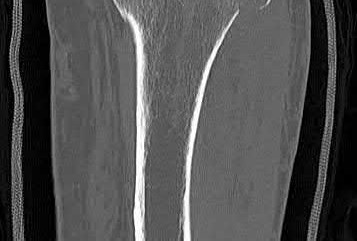

Figure A is an AP radiograph of the forearm following ORIF of a both-bone forearm fracture with a long straight plate which fails to restore the anatomic radial bow. Figure B is a lateral radiograph of the same patient demonstrating fracture fixation with a long straight plate. Illustration A demonstrates the method for determining radial bow. A line from the sigmoid notch to the bicipital tuberosity is drawn (Y). A perpendicular line is drawn from Y to the point on the radial with maximal bow (a) (This number is usually 7%). The point of this intersection to the bicipital tuberosity is marked (x). The location of maximal bow is x/y (This number is usually 60%).